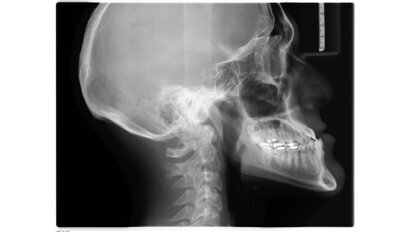

Kan reflux gebitsslijtage veroorzaken? Speekselonderzoek met sensor in de mond